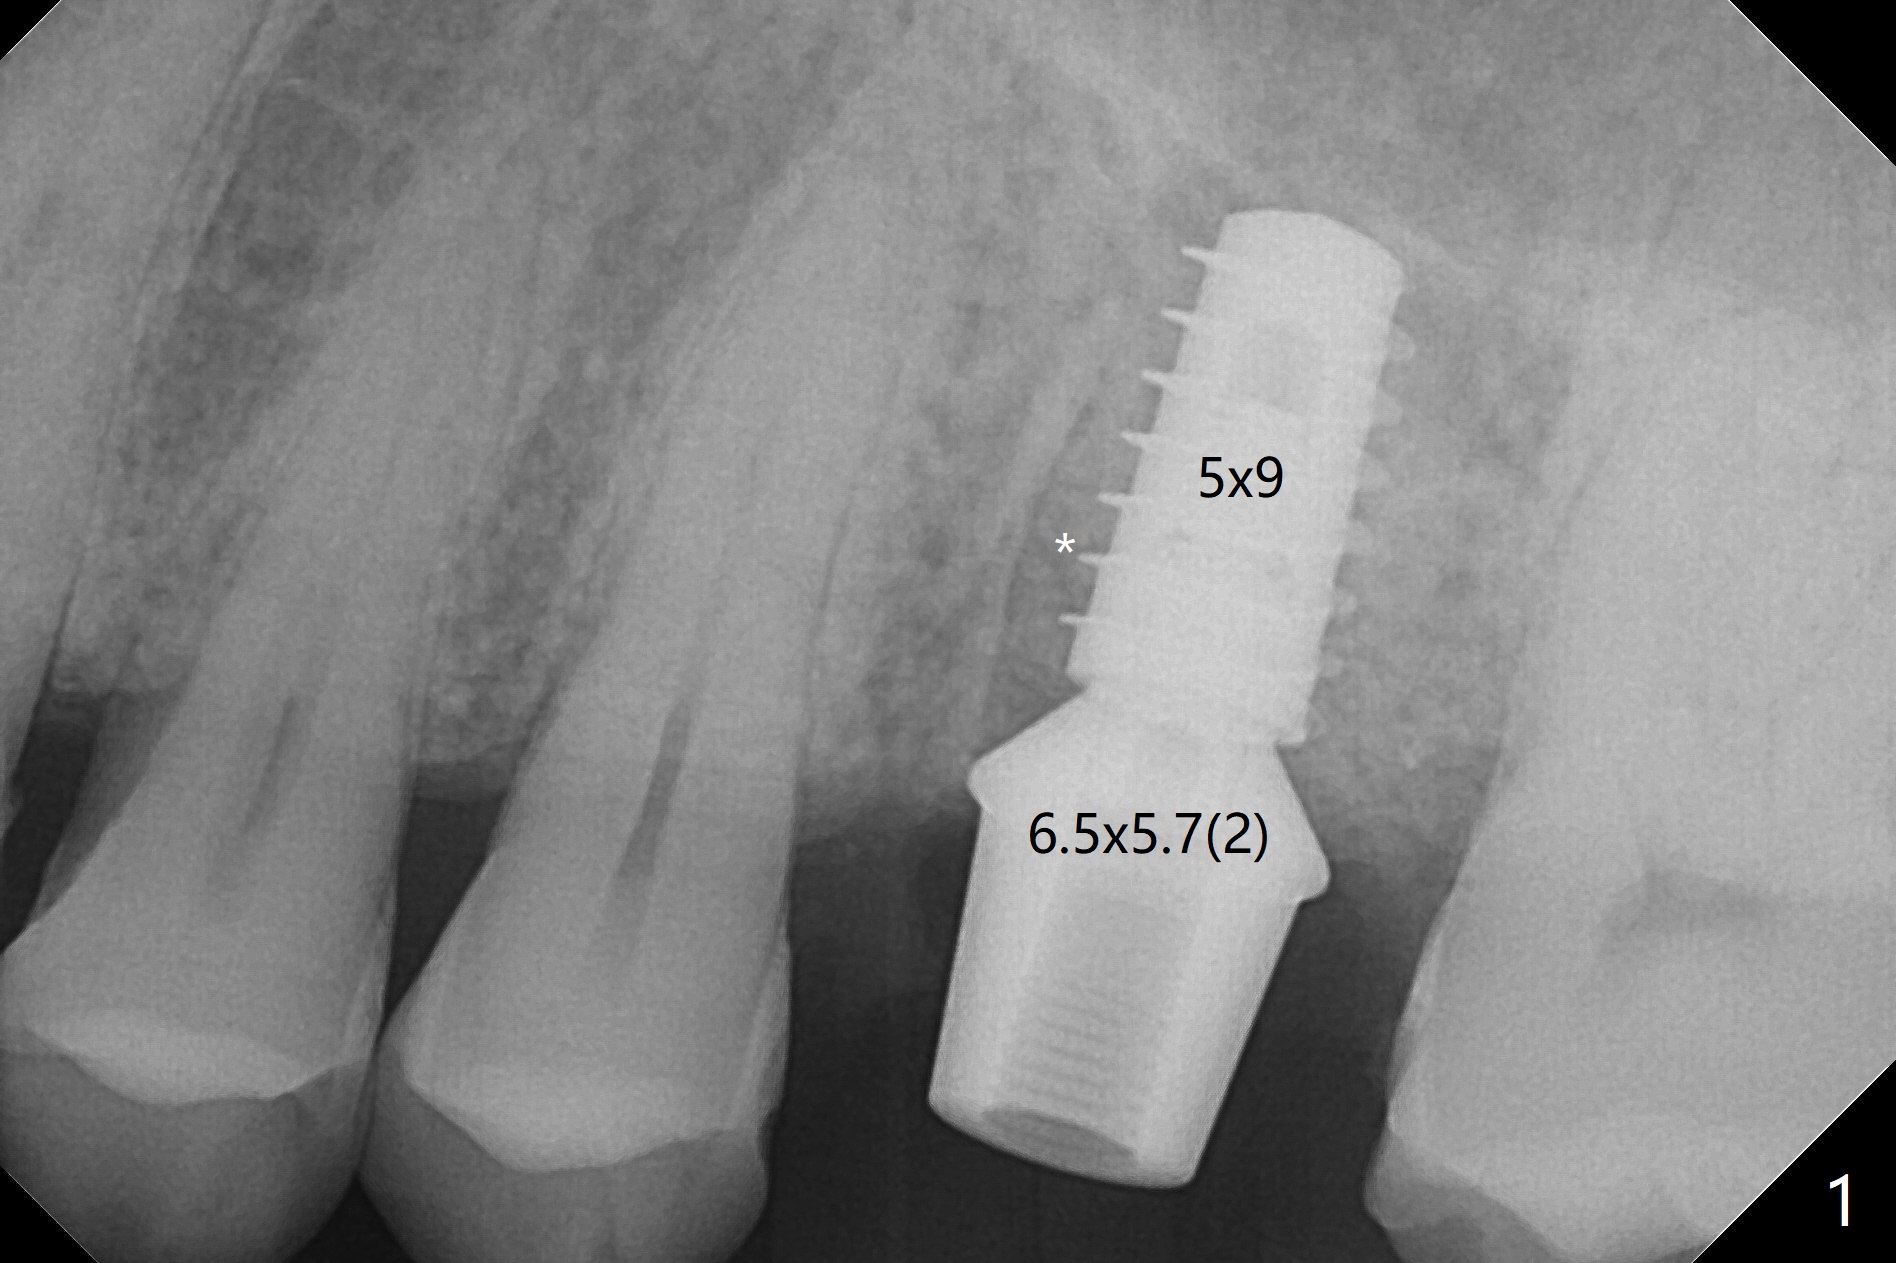

With modification of drill sequence in the last 3 steps (4.5x7.3, 4.0x8.5 and 3.5x10 mm drills) at #14 and sinus lift (Fig.1), a 5x9 mm implant is placed with ~ 50 Ncm following back up twice. Sticky bone mixed with autogenous bone (Fig.1,2 white *) is placed in the sockets before and after placement of a 6.5x5.7(2) mm abutment. Since the palatal gingival margin is recessive (Fig.3 ^), a palatal socket shield retains to prevent further recession (Fig.4 in the end of periodontal probe). Because the margin of the abutment is low, it changes to one with longer cuff (Fig.5). An immediate provisional is fabricated (Fig.6,7 P). The bone graft is indistinguishable from the original alveolus 9 months postop (Fig.8 *). The palatal socket shield is exposed 10 months postop (Fig.9 <). Since the implant is intentionally placed buccal; the sheath is not essential.